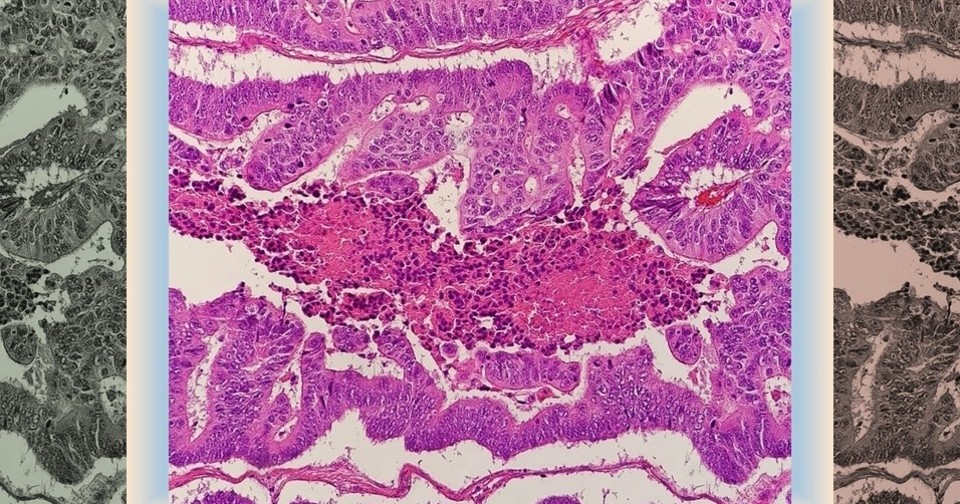

Одним из важнейших процессов в развитии новообразований (в том числе злокачественных) считается образование новых кровеносных сосудов в опухоли из ранее существовавшей сосудистой сети, или ангиогенез. Поэтому ингибиторы ангиогенеза (например, ингибиторы фактора роста эндотелия сосудов) активно используются при терапии различных видов опухолей. И хотя механизм их действия предполагает потенциальное повреждение стенки сосудов, данные, оценивающие связь между применением этих препаратов и расслоением артерий или аневризмами, ограничены отчетами об отдельных случаях и докладами по фармаконадзору.

Поэтому группа ученых во главе с Пернель Нуаз (Pernelle Noize) из Университета Бордо провела исследование по типу «случай — контроль» с использованием данных из электронных медицинских карт 2145 пациентов с метастатическими колоректальными опухолями. У 195 из них (0,6 процента от общей выборки всех, кто получал ингибиторы ангиогенеза) зарегистрированы случаи расслоения или аневризмы артерий. Эти случаи сопоставили с 1950 пациентами контрольной группы. Среди изученных препаратов значились бевацизумаб, афлиберцепт, рамуцирумаб, регорафениб, цетуксимаб и панитумумаб.